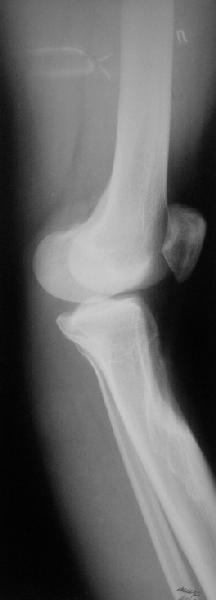

Жалобы у нее на появившиеся боли в колене при нагрузках. Признаков воспаления не было и нет, опухолевого роста также. Природа дефекта в области бугристости не очень понятна. Дополнительно сделали КТ и боковой снимок в максимальном разгибании - все в приложении.

Рекурвации в коленном суставе нет, есть рекурвационная деформация проксимальной части голени.

За точку отсчёта при планировании коррекции надо взять латеральный снимок в максимальном стрессе на разгибание. Остеотомию необходимо произвести тот час дистальнее места прикрепления собственной связки надколенника.(очень важно)

Ориентировачно на боковой проекции угол между тибиальным плато и анатомической осью тибии на передне-боковой проэкции должен быть порядка 90 градусов, а на боковой 80, кроме того на боковой проэкции при выпрямленном колене передний кортекс большеберцовой кости должен находиться на одной линии с передним кортексом бедренной кости.